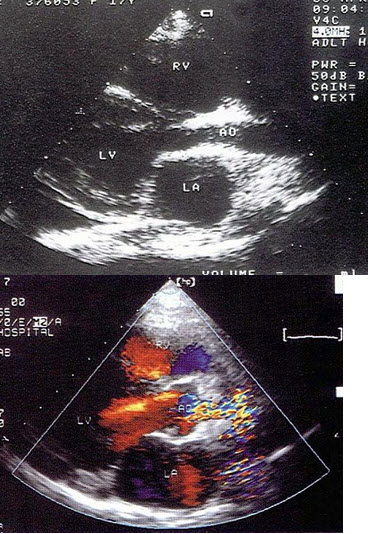

80、单项选择题

该图蓝色血流信号表示()

A.动脉血

B.静脉血

C.血流方向背离探头

D.血流方向朝向探头

E.以上均不是